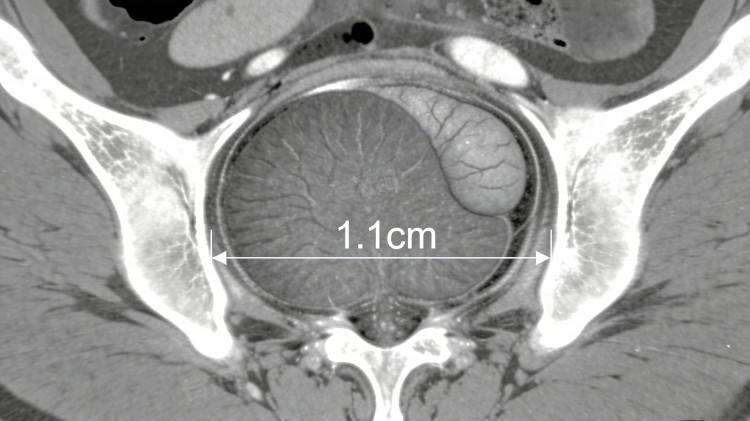

前列腺增大1.1厘米属于轻度增大,需结合具体病因针对性处理,其成因涵盖非疾病因素与疾病因素,轻重程度差异较大,如年龄增长生理性增生、前列腺增生症早期等。

5、前列腺占位性病变:少数情况下,前列腺增大1.1厘米可能与前列腺结节、肿瘤相关,可能伴随血尿、体重下降等症状,需高度警惕。立即完善前列腺特异性抗原检查、前列腺增强CT,明确病变性质,必要时手术治疗,避免病情恶化。